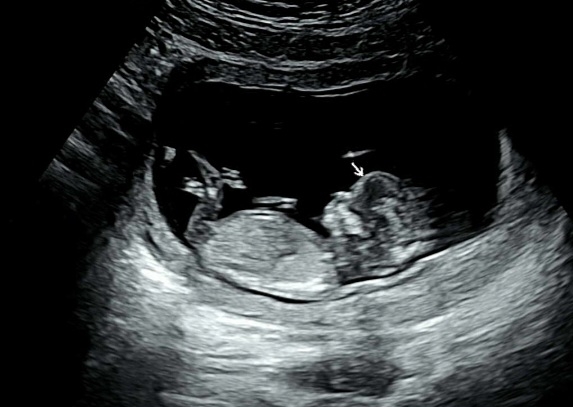

각도법봐주세요🥹소중한 의견부탁드려요❤️

너무 궁금해요... 성별 어떻게보이시나요??😳

다리땜에 생식기가 안보여요~~~~ 근데 애기 이마 넘이쁘네요 ㅎㅎㅎ